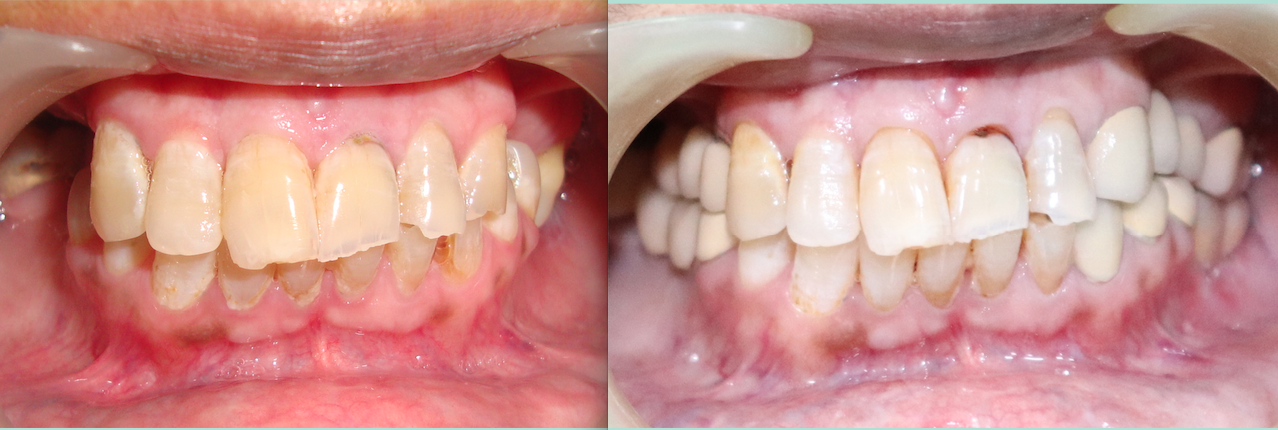

Single Tooth Replacement

Card image

Multiple Teeth Replacement